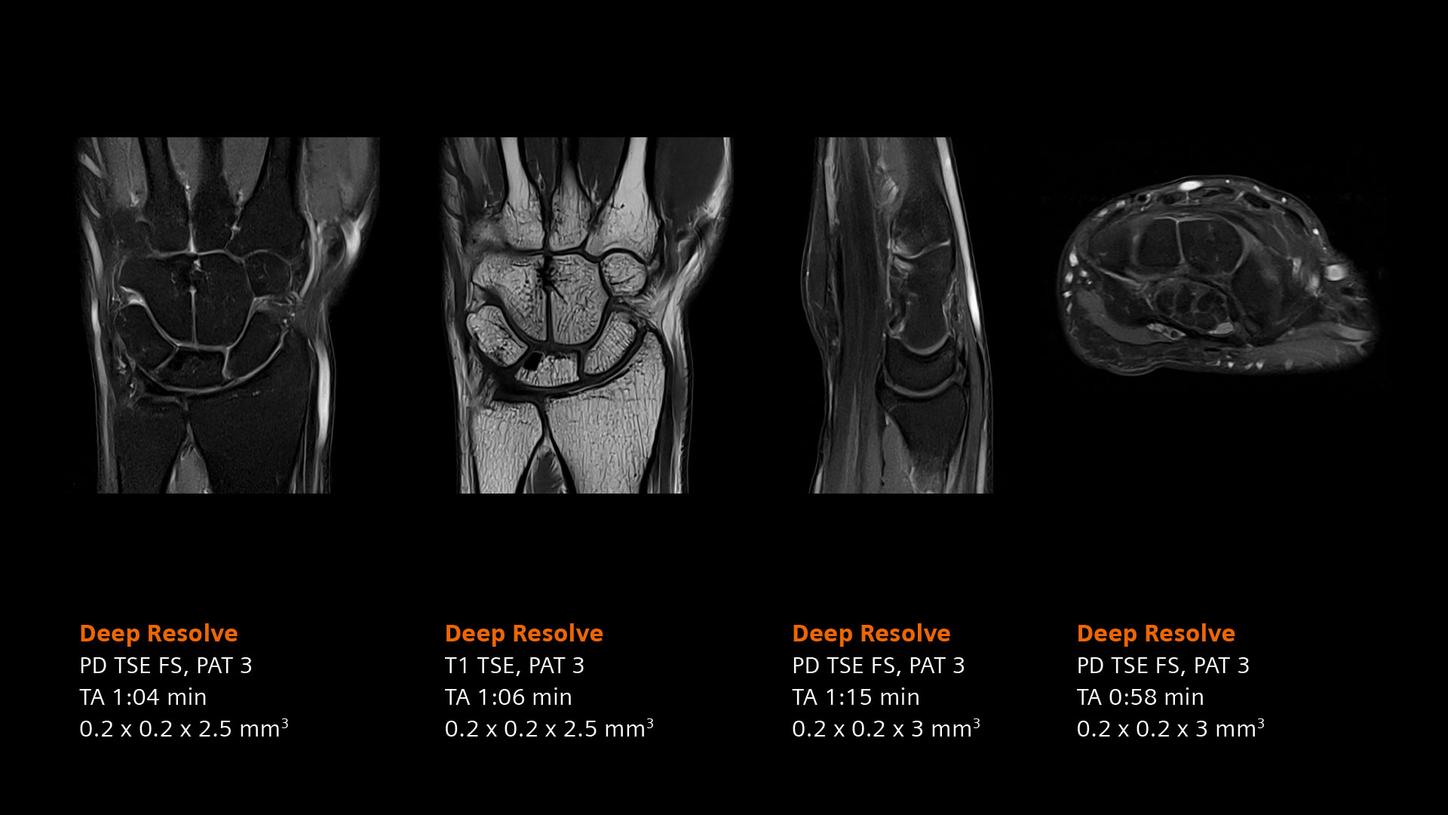

Deep Resolve will be at the forefront of the revolution in MRI acceleration. Deep Resolve will enable our fastest MRI, with images that will have extraordinary clarity, higher clinical productivity, and an even better patient experience. This transformational effect of Deep Resolve is now planned to expand to 3D5, unlocking a new dimension in MRI image resolution and speed.